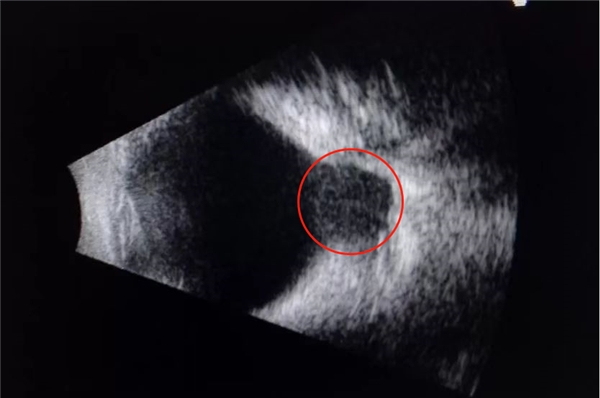

三、眼底巩膜后葡萄肿:眼球后部的伸张,若局限于一小部分时,从B超或者眼底照片中可以看到一个凹下去的深坑,称为巩膜后葡萄肿。后巩膜葡萄肿可能会诱发视网膜脱离或者是网膜下出血,导致患者视力的急剧下降。